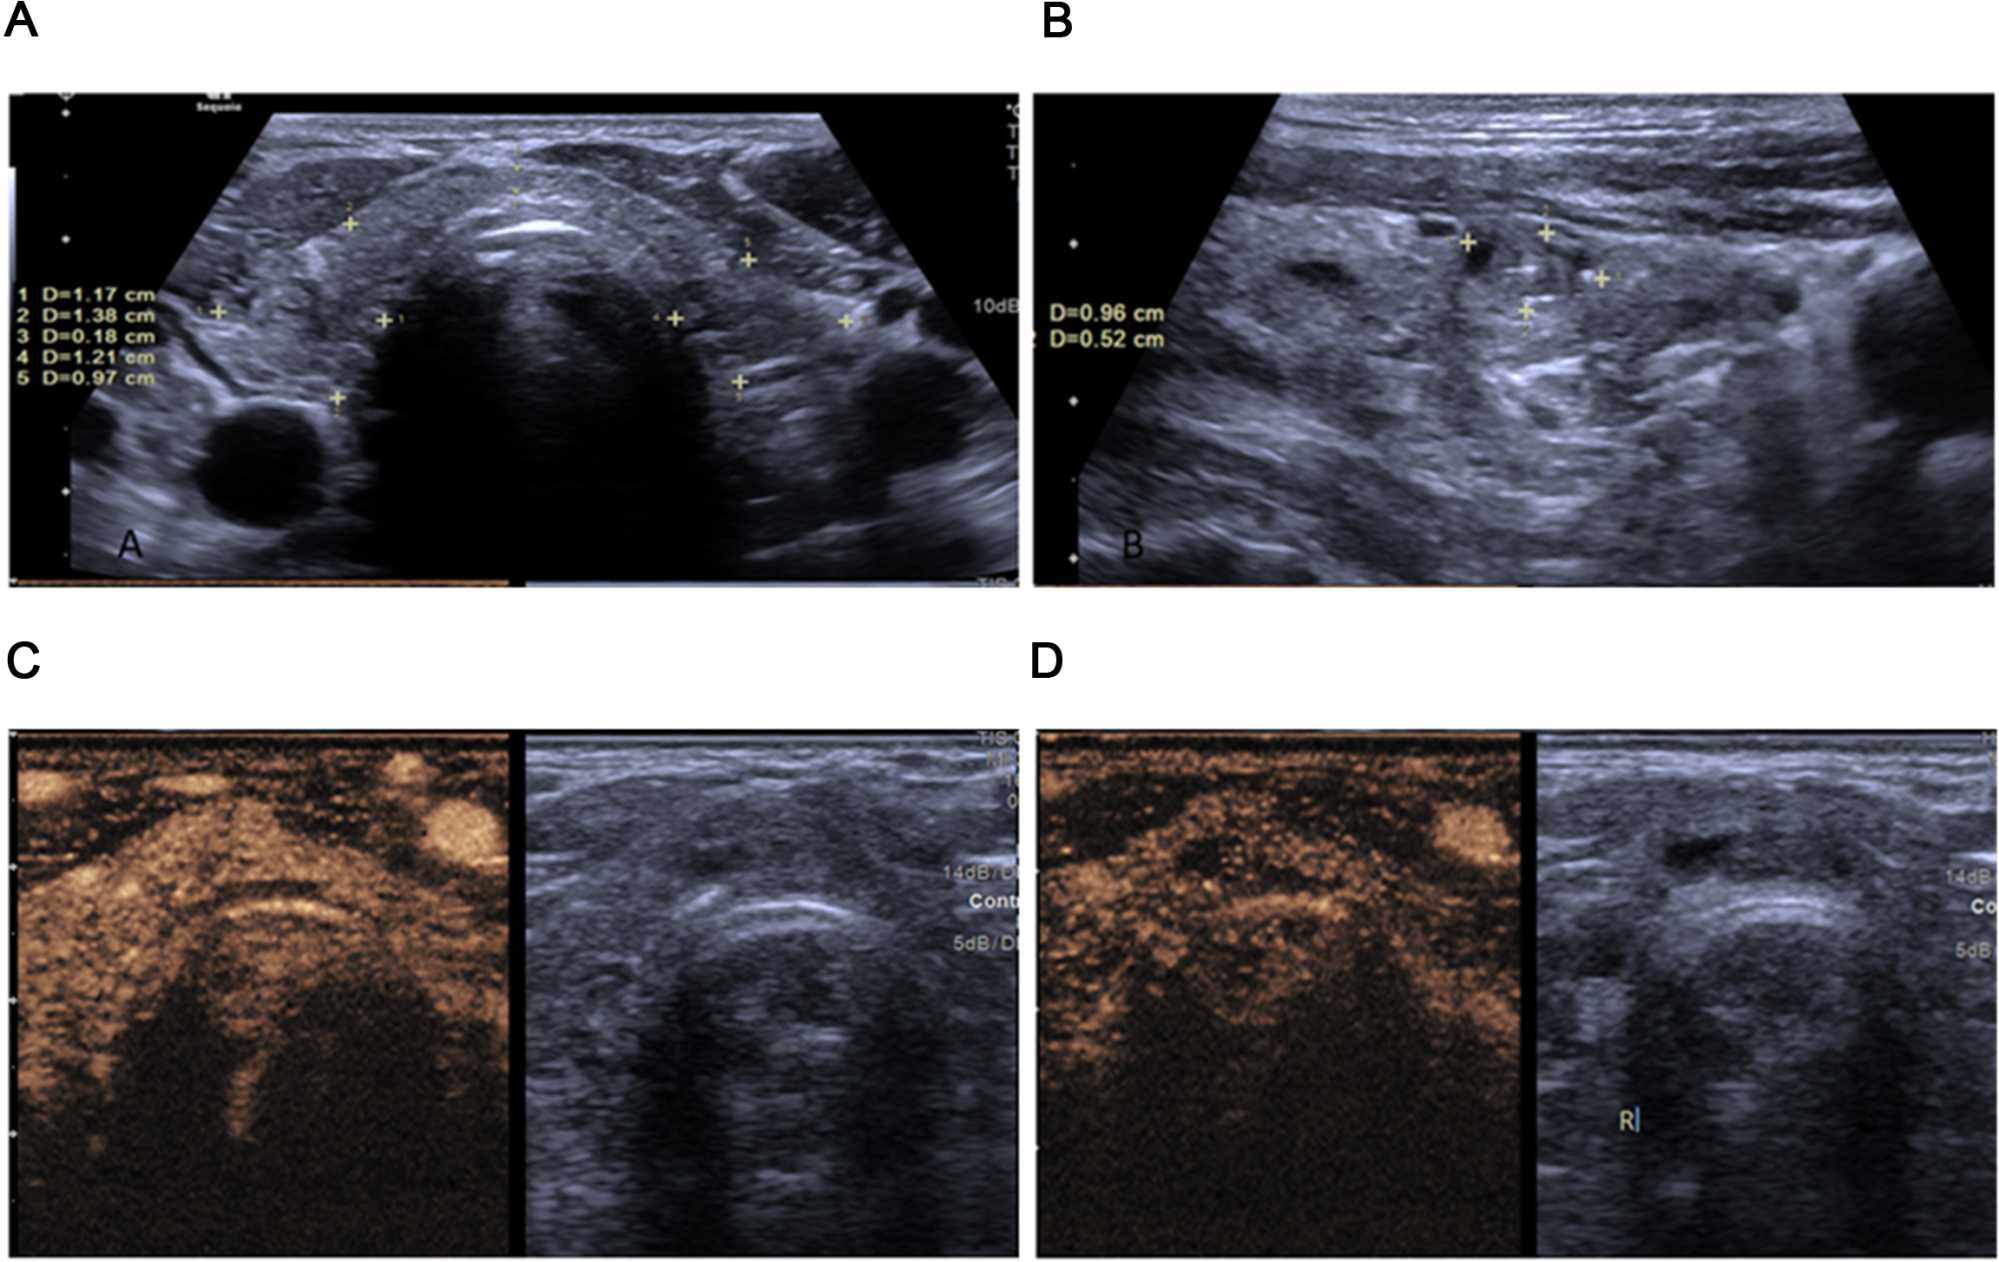

The primary outcome of this study was nodule inactivation following RFA. Of the 72 patients, 51 (70.8%) had complete nodule inactivation, while 21 (29.2%) had partial inactivation. Figure 2 shows nodule images of 2 patients before and after RFA. The two groups of patients had no significant differences in terms of age, gender, nodular diameter and volume (all p > 0.05). Those with complete inactivation had more calcification (p = 0.040), while those with partial inactivation had more vascularity (p < 0.001). Table 2. Analysis of changes in thyroid hormone levels between the two groups over a 6-months period showed no significant difference, although slight increase in TSH levels were seen within groups over the same period. Table 3. Figures 2-4 show sonographic images of a benign nodule pre RFA, a partially inactivated nodule and a completely inactivated nodule respectively.

Figure 2. Pre-ablation benign nodules in the right and left thyroid lobes based on the cytological results. The sonographic features included (A, B) hypoechoic solid nodules, with clear margins on grayscale mode (C, D) Application of CEUS shows a scanty enhancement in the right nodule. Thyroid nodule RFA: Radiofrequency Ablation, CEUS: contrast-enhanced ultrasound.